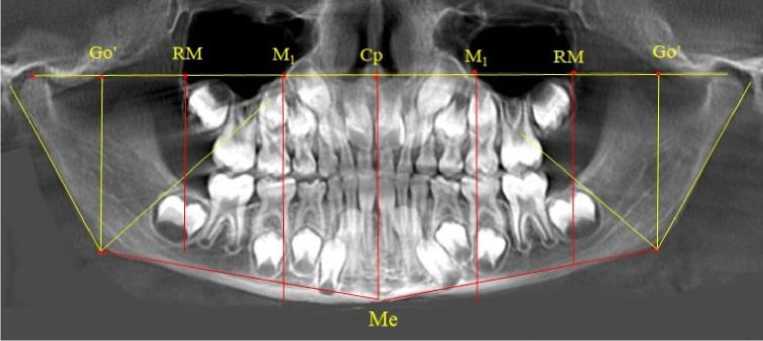

Расстояние между точками Go ´ и центральной точкой ( Central point ) Ср делили на коэффициент 1,5. Полученную расчетную величину откладывали от центральной точки на суставную горизонталь с обозначением точки (RM), от которой опускали перпендикуляр, который располагался в ретромолярной зоне и, как правило, проходил вблизи дистальных поверхностей задних зубов, ограничивающих зубоальвеолярные дуги. Кроме того, половина расстояния Ср-RM определяло положение молярной вертикали и точку на суставной горизонтали обозначали как М 1 (рис. 1).

Рис. 1. Анализ ортопантомограммы ребенка в периоде сменного прикуса при определении положения дистально расположенных зубов

Отношение отрезка суставной горизонтали от центральной точки (Ср) до проекции гонио-нальной точки (Go´) к коэффициенту 1,5 определяло расположение отправного точечного ориентира (RM) для построения ретромолярной вертикали перпендикулярно к суставной горизонтали. Особенностью исследуемого возрастного периода было то, что зачаток первого верхнего постоянного моляра при оптимальном окклюзионном соотношении располагался впереди ретромолярной вертикали. Данное обстоятельство свидетельствовало о благоприятном расположении зачатка, что в последующем обеспечивало его прорезывание по мере формирования корней. Кроме того, указанный размер (Ср-RM) определял зубоальвеолярный размер верхней челюсти (правой и левой). Молярная вертикаль, исходящая из молярной токи (М1), проходила через дистальные поверхности первых молочных моляров обеих челюстей (рис. 3).

Рис. 3. Анализ ортопантомограммы ребенка 4 лет в периоде прикуса молочных зубов